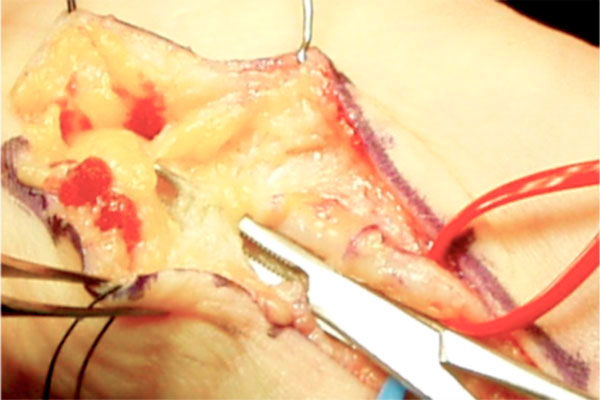

La cirugía consiste en liberar el nervio cubital con los siguientes pasos:

1.- incisión sobre el pisiforme,

2.- disección proximal del nervio y apertura del canal de Guyon,

3.- disección de las ramas distales llegando desde la rama motora a la arcada del abductor del 5º dedo y

4.- en caso de existir una causa concreta de compresión realizar el tratamiento del proceso mediante extirpación, reparación, etc… (figuras 6-8).

Figura 6: incisión de abordaje

al canal de Guyon.

Figura 7: liberación a nivel proximal.

Figura 8: disección a nivel distal de las ramas del nervio cubital.